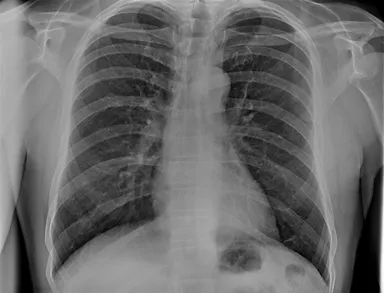

TRB 9020Hで撮影した胸部レントゲン写真

※90 kV HP mode, 1.65 mAs, 0.06 sec